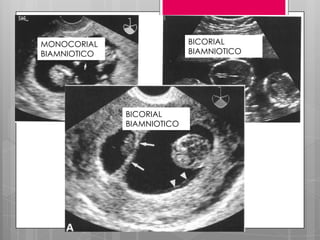

DIAGNOSTICO

 Mediante ecografía.

 Tamaño del útero es grande para la EG

calculada. (diferencia de 4 cm).

 1ra debe determinar la corionicidad –

morbimortalidad asociada a GMN es dif de

la GDC = se determina a las 9 y 10 SDG.

BIAMNIOTICOS BICORIONICOS

MONOCORIAL BIAMNIOTICO

MONOCORIAL

MONOAMNIOTICO

BICORIAL

BIAMNIOTICO

DIAGNOSTICO  Mediante ecografía. Tamaño del útero es grande para la EG calculada. (diferencia de 4 cm).  1ra debe determinar la corionicidad – morbimortalidad asociada a GMN es dif de la GDC = se determina a las 9 y 10 SDG.